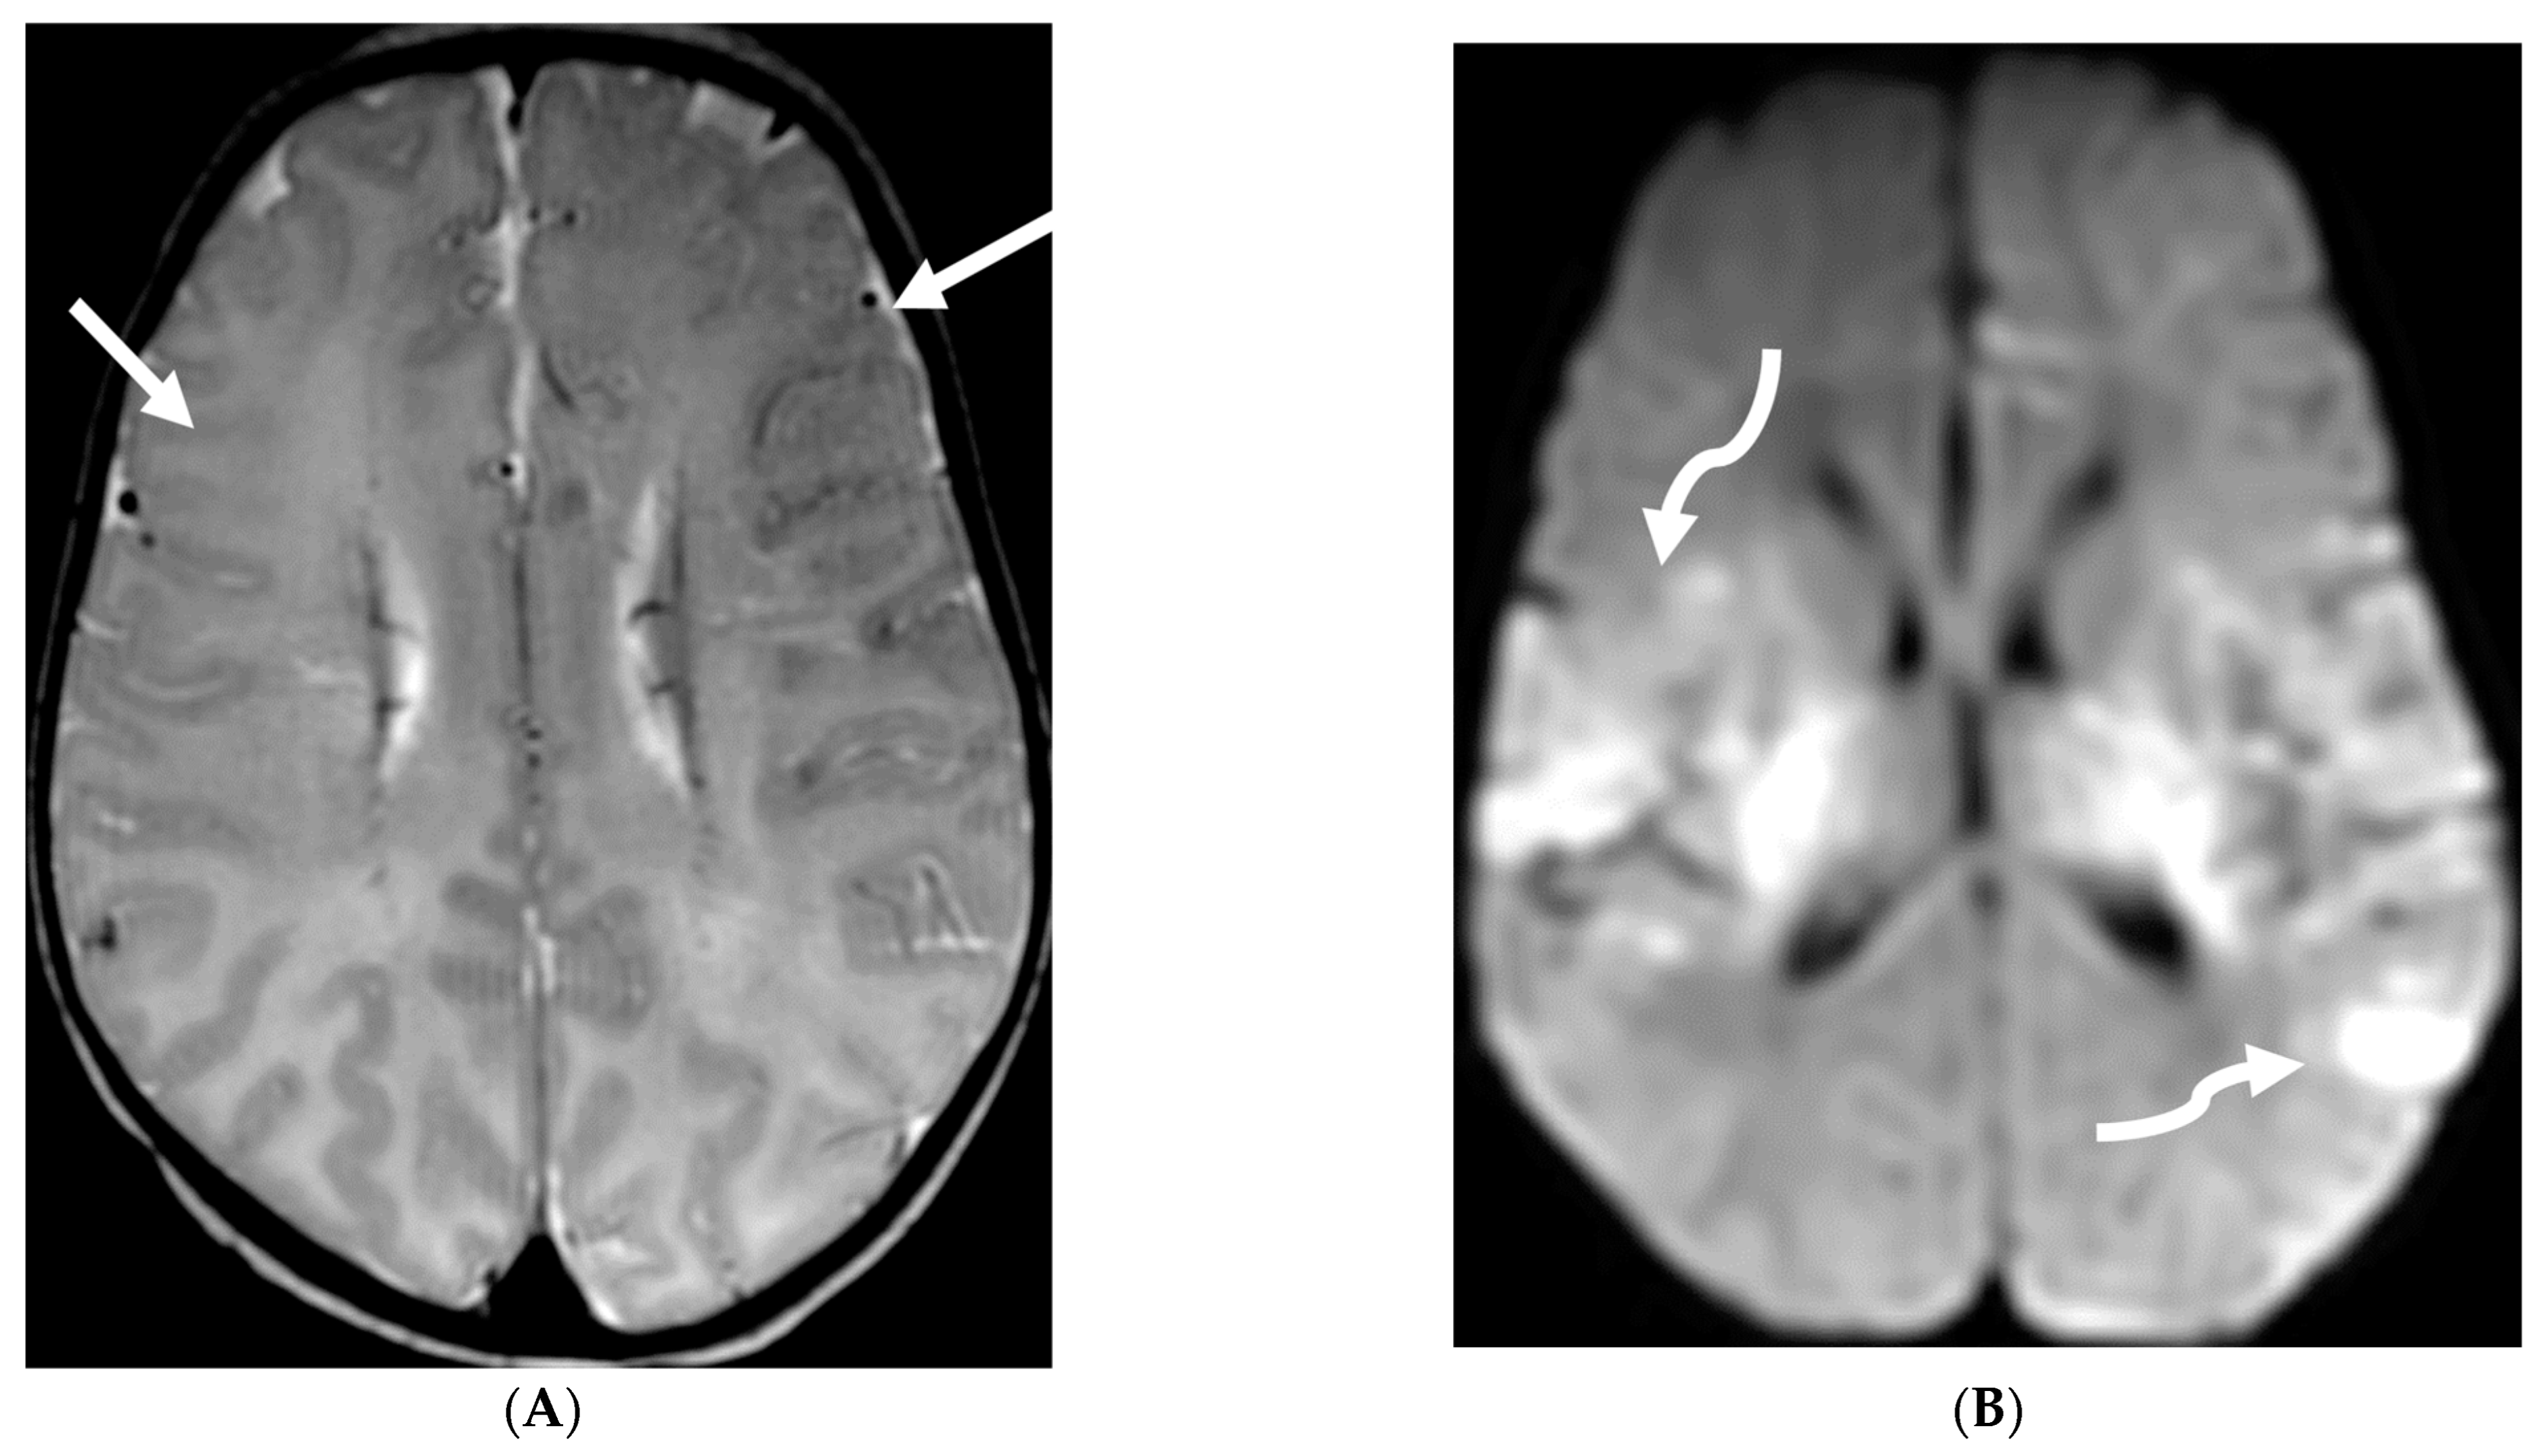

HSV 2 typically causes diffuse cortical involvement with diffusion restriction, loss of gray white matter differentiation and basal ganglia involvement in early stages [98]. HSV 1 typically occurs in older children and adolescents and leads to asymmetric temporal lobe involvement with relative sparing of the basal ganglia (Figure 19).

Figure 19.

17-day-old girl with seizures. Axial T2 (A), axial DWI (B), axial T1 post contrast (C), short TE spectroscopy (D) and coronal T2 (E): There is loss of gray white matter differentiation indicating edema in bilateral frontal lobes (arrows). Extensive ischemic changes involving bilateral frontal, bilateral parietal lobes, bilateral perisylvian regions, bilateral thalami (curved arrows). Extensive LME is identified in the effected regions (dashed arrows). Abnormal elevation of lipid/lactate in both basal ganglia and white matter (open arrows). The above constellation of features are concerning for meningitis/cerebritis. Follow up MRI 5 weeks later demonstrates evolution of extensive ischemic changes into extensive cystic encephalomalacia and gliosis in the supratentorial brain, with ex vacuo enlargement of the ventricular system. CSF analysis: HSV-2.